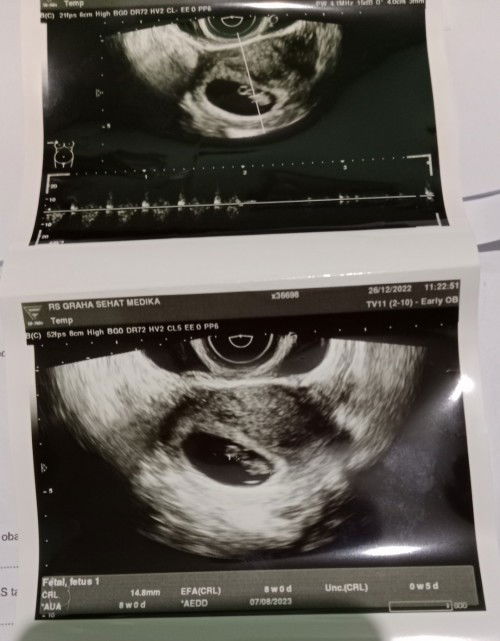

Hallo bun sekedar sharing ,ini hasil usg saya usia kehamilan 8 minggu,,udh ada janin dan detak jantungnya alkhamdulillah bun,,tapi wajar gak kalo buat makan/minum lidah terasa pahit??kalo buat bersin/batuk perut terasa nyeri kencang banget Adakah yang sama bun??#seriusnanya #bantusharing #ingintahu #firstmom #pleasehelp #firstbaby